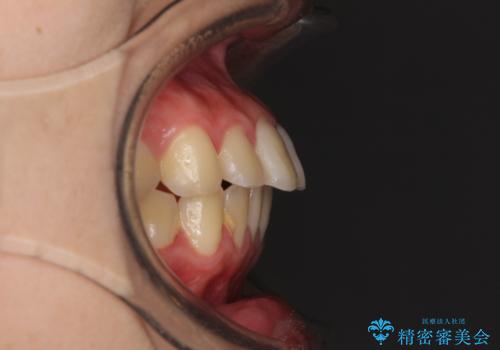

歯のがたつきはあまりなかったのですが、口唇が閉じずらく、口元の突出感が確認できました。

上下左右の歯を1本ずつ抜歯して、そのスペースを利用して口元を引っ込める計画としました。

口元を下げて口唇を閉じやすくする場合、抜歯矯正をお勧めさせていただくことが多いです。